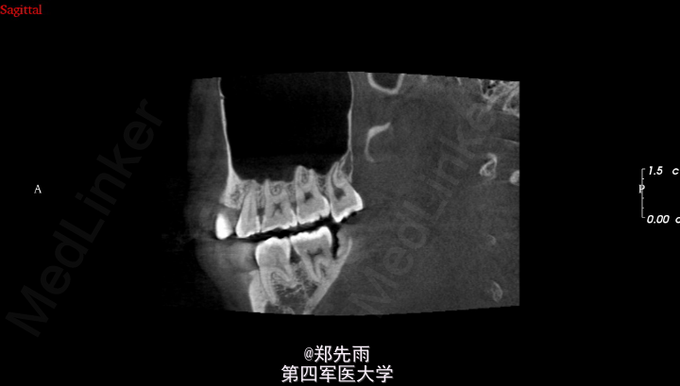

前牙区埋伏牙+上颌窦气化严重

13先天性埋伏阻生,前鼻棘下方埋伏牙,行CBCT检查提示均位于唇侧,但CBCT提示双侧上颌后牙牙根不同程度位于上颌窦内。

诊断:13埋伏阻生,上颌埋伏多生牙。 处理:住院拔除上颌埋伏牙,分次拔除正畸减数牙。与患者术前充分沟通上颌窦穿孔、上颌窦瘘的可能。